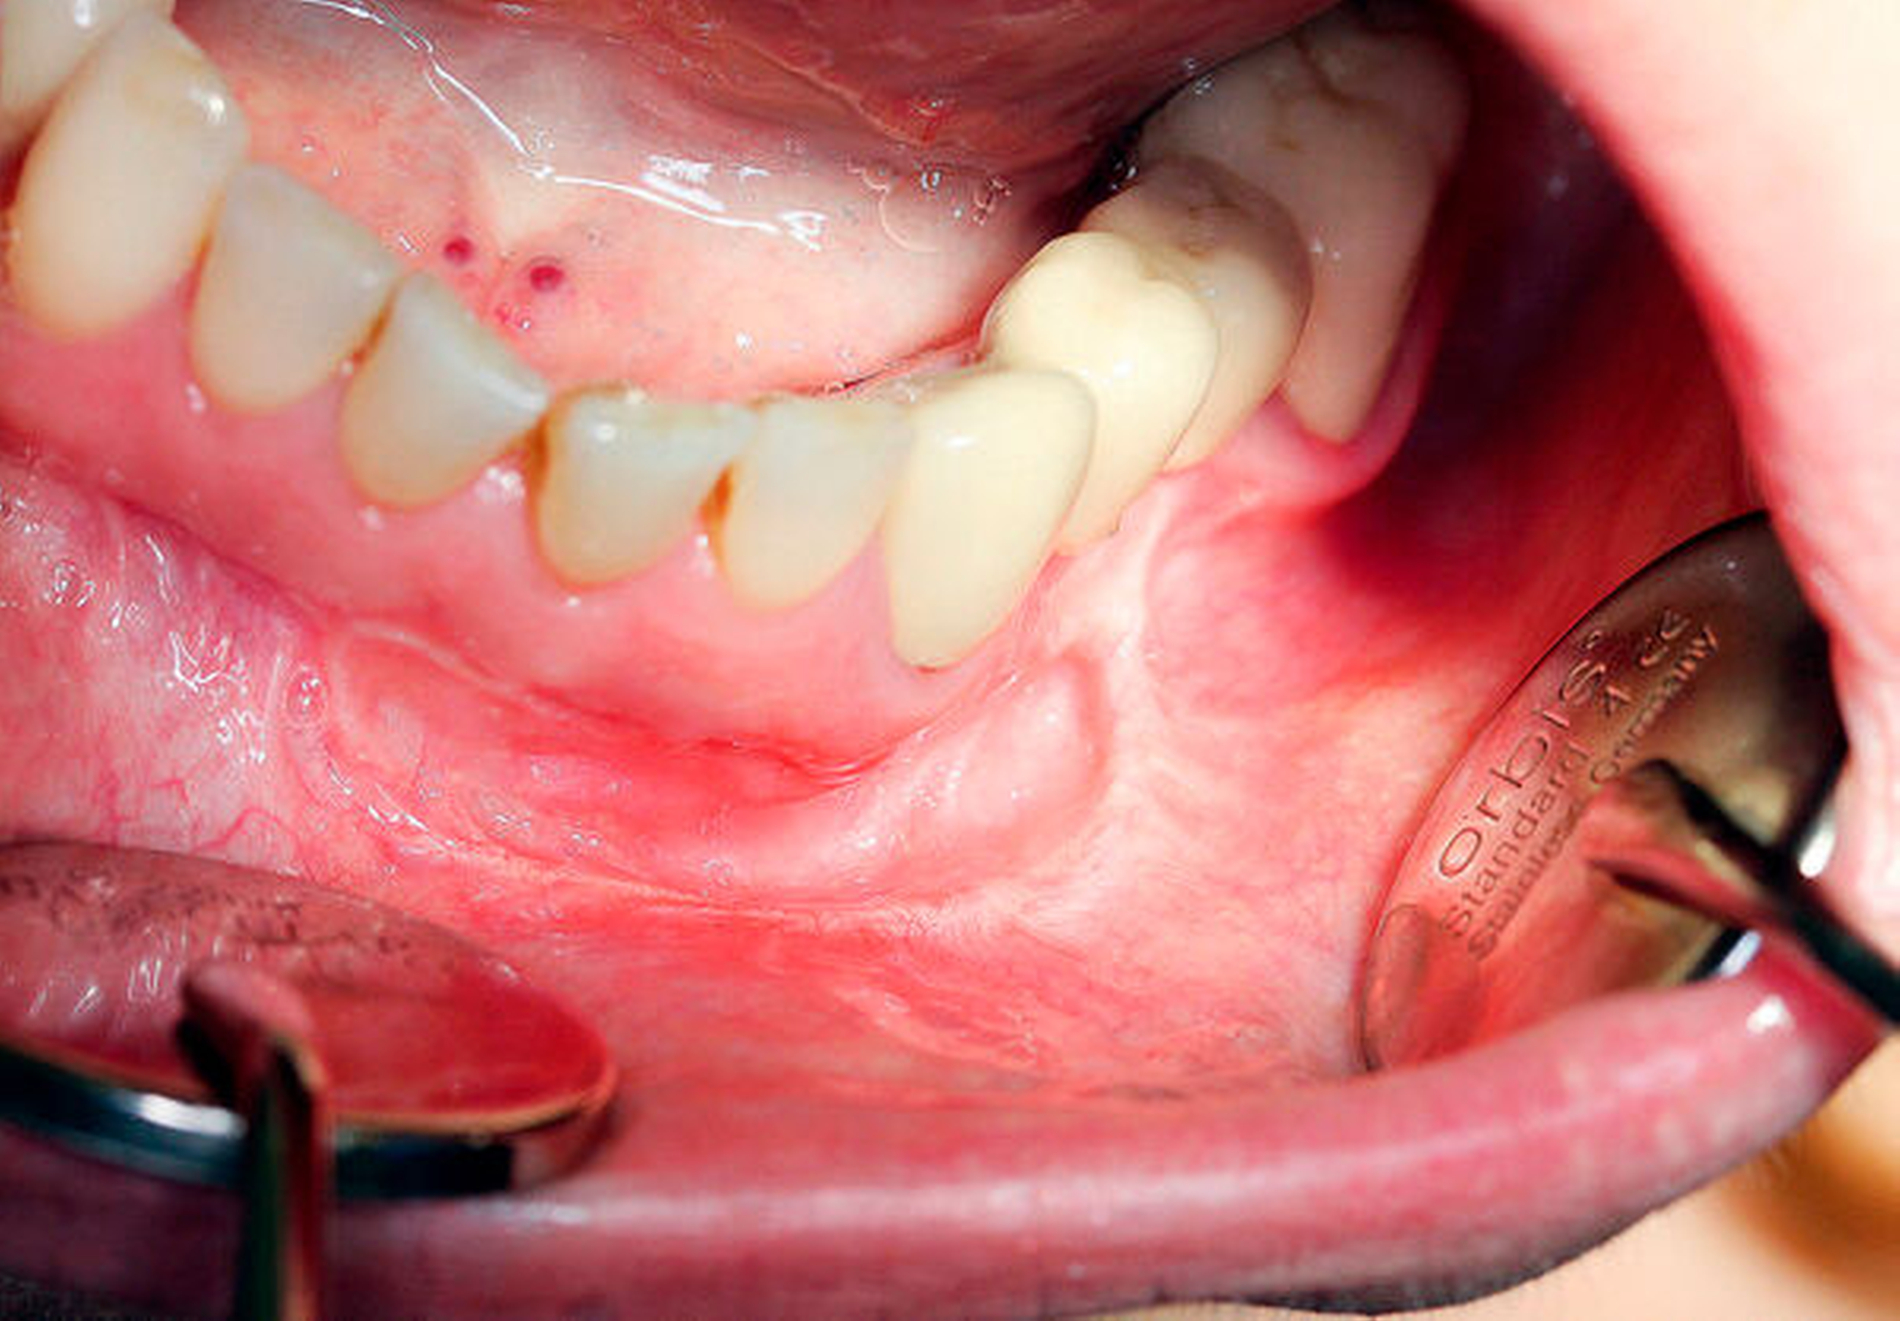

Diese stellte sich gelb-gräulich dar und ließ sich vom Gewebe nur schwer abgrenzen. Daraufhin erfolgten die Resektion (Abbildung 4) unter Facialismonitoring sowie die primär plastische Rekonstruktion.

Aufgrund der fehlenden Symptomatik entschied man sich dort zunächst für ein abwartendes, konservatives Prozedere. Im weiteren Verlauf erfolgte bei narbig verzogenem Vestibulum im Bereich der Unterlippe eine Lösung der funktionsbehindernden Narben mit Vestibulumplastik mittels Mundschleimhauttransplantat. Nach unproblematischer Einheilung zeigte sich die Patientin zwölf Monate postoperativ beschwerdefrei bei reizlosen intraoralen Verhältnissen und regelrechtem Neurostatus.